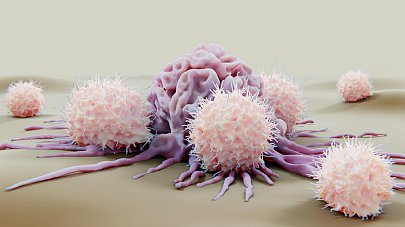

Иммунотерапия

Метод лечения рака, при котором для борьбы с опухолью активизируется иммунная система

Целевая (таргетная) терапия

Препараты, которые воздействуют только на раковые клетки, не затрагивая здоровые